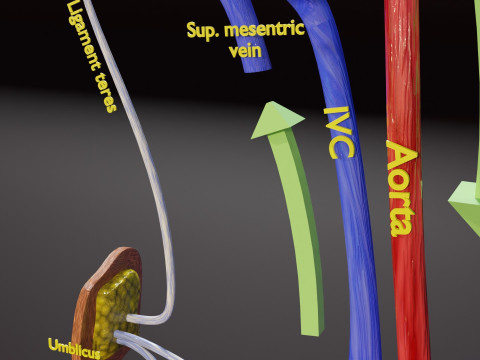

The model meshes include adult circulation versus circulation in Tetralogy of Fallot (TAF), arrow labels and text labels. The blood flow in a patient with Tetralogy of Fallot is outlined in this model. To contrast it to normal blood circulation a separate model of normal circulation is included. The Tetralogy of Fallot (OVER RIDING OF AORTA, PUL STENOSIS, VENTRICULAR SEPTAL DEFECT, RIGHT VENTRICULAR HYPERTROPHY), fossa, ligament teres , venosus, and arteriosus are duly depicted with proper labelling and blood flow directional arrows. Excellent model for teaching, demonstration and knowlegde of human body. The models include both procedural and image textures blend files separately. The texture file include diffuse, roughness and normal png and jpeg based on non overlapping UV maps.